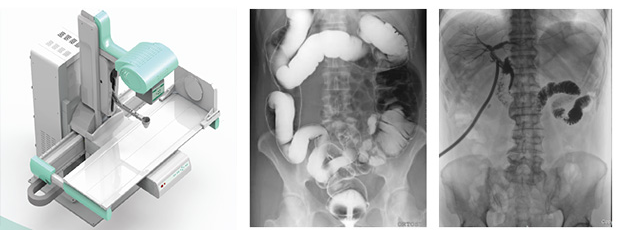

x線數(shù)字胃腸機(jī)

x線數(shù)字胃腸機(jī)主要用來進(jìn)行咽喉部、食道、胃、十二指腸、空回腸及結(jié)腸各種疾病的造影診斷。這款醫(yī)用設(shè)備由高壓發(fā)生器、球管、影像增強(qiáng)器、電動(dòng)檢查床曝光控制臺(tái)和數(shù)字處理工作站組成。

x線數(shù)字胃腸機(jī)的實(shí)質(zhì)其實(shí)是多功能數(shù)字成像系統(tǒng),采用影響增強(qiáng)器把X光轉(zhuǎn)化為可見光,由電荷耦合器將可見光轉(zhuǎn)化為視頻信號(hào),轉(zhuǎn)監(jiān)視器顯示,是一種新的成像方式。流程簡單,操作方便,既達(dá)到診斷目的又減輕病人痛楚。主要特點(diǎn)是準(zhǔn)確、高效、全能。

采用的平板探測器成像性能優(yōu)異,像素148微米,灰階16bits,圖像清晰準(zhǔn)確,為臨床診斷提供了準(zhǔn)確的依據(jù)。

超大視野的x線數(shù)字胃腸機(jī)

17”×17”(43cm×43cm)碘化銫非晶硅動(dòng)態(tài)平板探測器。超大視野全腹覆蓋。記錄一個(gè)成年人的吞咽過程無須移動(dòng)平板,不產(chǎn)生偽影。對于一些身材高大的患者,無論是頭端,還是下肢,均可全部覆蓋,拍攝無遺漏。

一機(jī)多能,既可以完成消化道造影、靜脈腎盂造影等各種造影檢查,又可以完成DR圖像的拍攝。保證無論靜態(tài)或動(dòng)態(tài)圖像都完美無缺 。